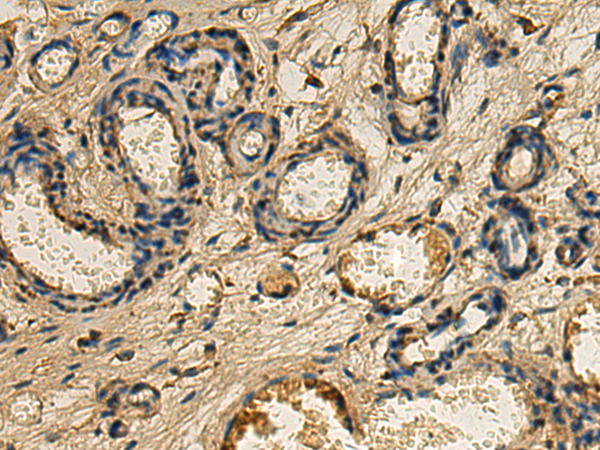

分类: 科研抗体货号: P01660别名: PP2CA; PP2Calpha; PP2C-ALPHA应用: WB,IHC反应种属: Human, Mouse, Rat